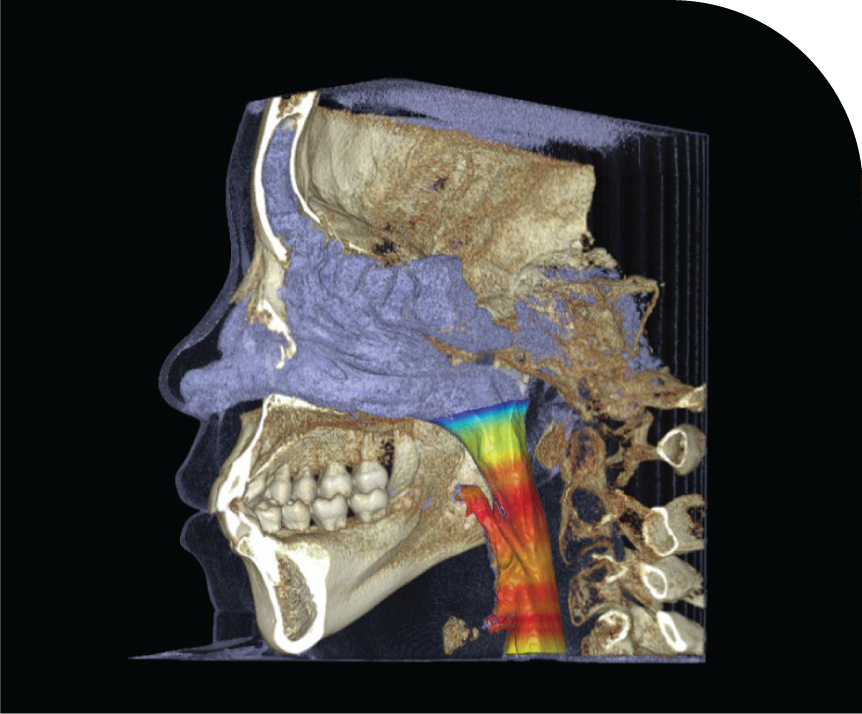

AIRWAY

Advanced Airway Imaging for Dental Treatments

We provide precise and comprehensive assessments of the airway using state-of-the-art imaging technology.This assists you in diagnosing and planning treatments for sleep apnea, orthodontics, and other dental-related airway issues. Our high-quality imaging ensures accurate visualisation, helping you deliver effective and targeted patient care. Enhance your treatment outcomes with our expert airway evaluation support.